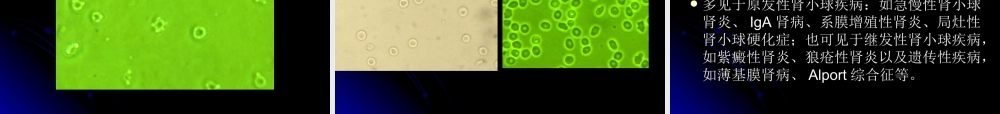

尿液有形成分检查的尿液有形成分检查的临床应用价值临床应用价值北京协和医院检验科张时民北京协和医院检验科张时民尿液是机体内具有重要意义的体液尿液是机体内具有重要意义的体液尿液常规检查是临床基础检验尿液常规检查是临床基础检验((常规检查常规检查))的重要内容之一的重要内容之一是临床上重要的过筛检查手段之一是临床上重要的过筛检查手段之一是评估肾脏疾病最常用的和不可取代的首是评估肾脏疾病最常用的和不可取代的首选检验项目之一选检验项目之一是普及和应用面非常广泛的实验内容之一是普及和应用面非常广泛的实验内容之一是操作简便、快速、无须昂贵仪器、费用是操作简便、快速、无须昂贵仪器、费用低廉、易于取得、无痛检查方法之一低廉、易于取得、无痛检查方法之一尿液常规检查,也称尿液一般检查,现在尿液常规检查,也称尿液一般检查,现在更流行的称呼是尿液分析(更流行的称呼是尿液分析(UrinalysisUrinalysis))《《中华检验医学大辞典中华检验医学大辞典》》对尿液分析的定对尿液分析的定义为:“用目测、理学、化学、显微镜及义为:“用目测、理学、化学、显微镜及其他仪器对尿液标本进行分析,以达到对其他仪器对尿液标本进行分析,以达到对泌尿、循环、肝、胆、内分泌系统等疾病泌尿、循环、肝、胆、内分泌系统等疾病进行诊断、疗效观察及预后判断等的目进行诊断、疗效观察及预后判断等的目的”。的”。尿液分析的全部内容应包括尿液理学检查、尿液分析的全部内容应包括尿液理学检查、化学检查和显微镜形态学检查三大部分。在化学检查和显微镜形态学检查三大部分。在完整的尿液分析过程中,不可对任何一项检完整的尿液分析过程中,不可对任何一项检验内容有所忽略,因为三大部分在临床疾病验内容有所忽略,因为三大部分在临床疾病的诊断和治疗中都有重要作用。的诊断和治疗中都有重要作用。一、尿液的理学检查一、尿液的理学检查包括对尿量、颜色、透明度、比密、气味、包括对尿量、颜色、透明度、比密、气味、(酸碱度)、渗透量、电导率等物理指标(酸碱度)、渗透量、电导率等物理指标进行分析检验。进行分析检验。血尿:肉眼血尿和镜下血尿血尿:肉眼血尿和镜下血尿脓尿:镜下脓尿和肉眼脓尿脓尿:镜下脓尿和肉眼脓尿混浊尿:注意区分脓尿、乳糜尿、结晶尿混浊尿:注意区分脓尿、乳糜尿、结晶尿二尿液的常规化学检查二尿液的常规化学检查尿液干化学检验项目主要有:尿液干化学检验项...